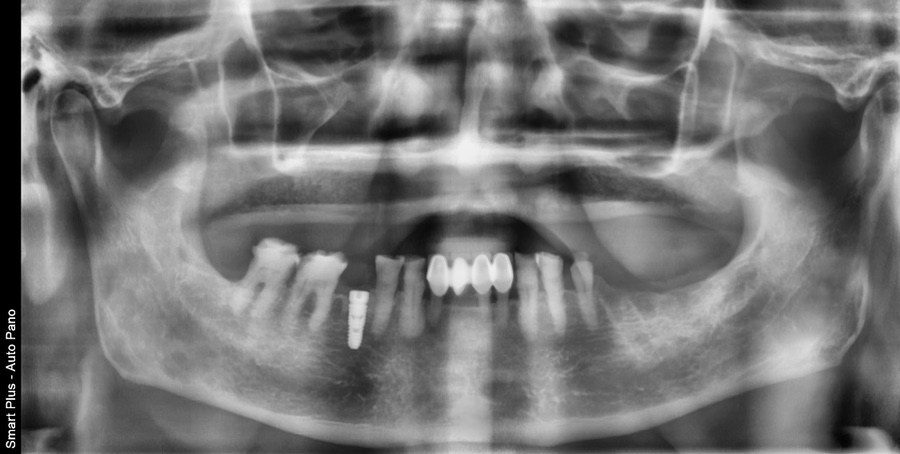

치료 후 사진 / 2025.06.19

복합적인 치과 치료는 어떻게 진행될까?

여러 문제가 동시에 존재하는 경우에는 단계적인 치료 계획이 필요합니다. 일반적으로는 다음과 같은 순서로 진행됩니다.

먼저 문제가 있는 치아에 대해 발치 또는 신경치료를 통해 염증과 통증의 원인을 제거합니다.

이후 치아가 상실된 부위에는 임플란트를 식립하여 기능을 회복할 수 있는 기반을 마련합니다.

그 다음 단계에서는 신경치료를 받은 치아나 손상된 치아에 크라운 보철치료를 진행하여 치아의 형태와 기능을 회복하게 됩니다.

마지막으로 전체적인 교합과 저작 기능, 심미적인 부분까지 고려하여 마무리하게 됩니다.

이 과정에서 중요한 점은 치료 순서를 체계적으로 계획하는 것입니다.

예를 들어 임플란트를 먼저 식립한 후 보철을 진행할 수도 있고, 반대로 신경치료와 보철을 먼저 진행해야 하는 경우도 있습니다.

이는 환자의 구강 상태에 따라 달라지기 때문에 정확한 진단이 선행되어야 합니다.